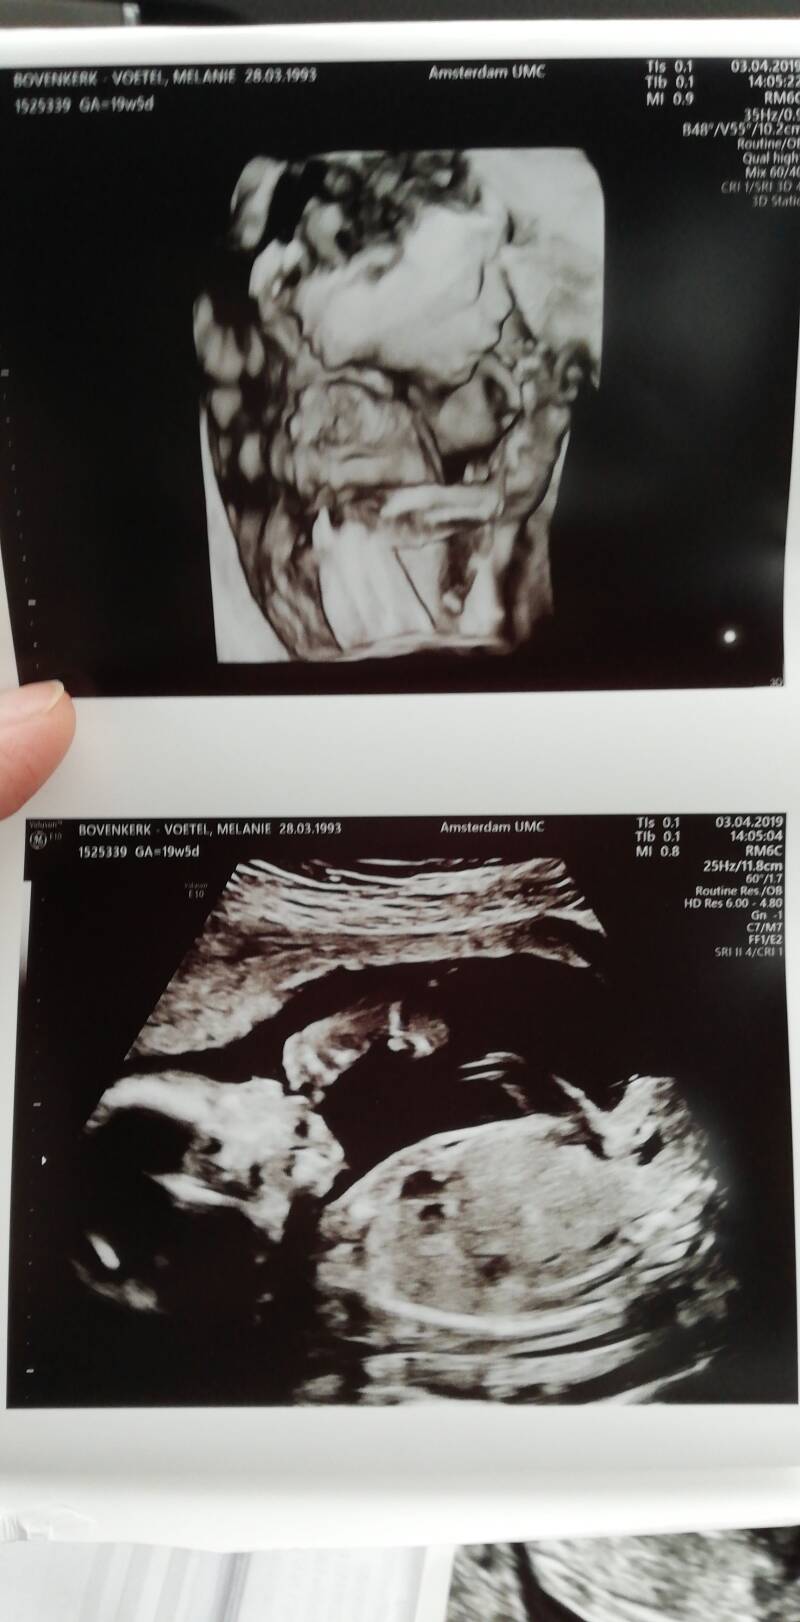

3 april, de dag van de GUO;  de uitgebreide echo.

Nou vandaag was de dag dan eindelijk hoor. Ondanks dat, vrij relaxt de nacht en ochtend doorgekomen. Het moment dat we voor het Umc reden kwam alles weer even binnen en dichtbij, maar meer kwa herinneringen aan Aiden. Eenmaal aangekomen op poli verloskunde waren we vrijwel direct aan de beurt. Eindelijk, maar super spannend, het moment van de waarheid. Ik heb zeker wel een half uur aan de echo gelegen en ze hebben letterlijk naar elk onderdeeltje gekeken waar een mens uit bestaat. Per onderdeel vertelde ze elke keer dat het er goed uit zag en dat het eruit zag  zoals het hoorde. Het enige afwijkende wat te zien was, was een cyste in de hersenen. Een Plexus choroïdeus cyste. Ze vertelde ons dat ze dit vaker zien, en dat je vroeger  altijd terug moest komen rond de 32 weken maar dat dit dan eigenlijk altijd verdwenen was. Aangezien dit het enige was wat afweek moeten wij ons hier geen zorgen om maken. Als het in combinatie met andere afwijkingen was zou het pas ergens op duiden. Een plexus choreoïdeus cyste is een kleine holte gevuld met vocht die in de zijhoornen van de hersenholtes ligt, waar het hersenvocht aangemaakt wordt. Deze cyste ontstaat tijdens het aanmaken van de hersenen, maar zal vanzelf moeten verdwijnen. Ik ga het overleggen met de verloskundige dat er opgelet wordt ivm als er andere afwijkingen of achterstanden ontstaan. Ik moet dit wel even laten bezinken maar ik ga het advies proberen aan te nemen om me er geen zorgen over te maken, alhoewel dat voor ons natuurlijk wel moeilijker is aangezien al eerder door specialisten is uitgesproken dat alles goed was en we ons geen zorgen hoefden te maken. Maar alles zag er prachtig uit, werkte naar behoren, ze bewoog heel goed en de specialisten daar waren er heel positief over. Pas in de auto op de terug weg toen de tranen ineens in mijn ogen sprongen, kwam alles even binnen. De uitslag, de spanning, de opluchting, de cyste, Aiden, de toekomst.. Alle gevoelens overweldigde me even. De grootste spanning is er voor nu in ieder geval wel even van af gelukkig. We hebben onszelf maar op een maccie getrakteerd, en nu maar even alles laten bezinken. Maandag weer naar de verloskundige in Hoorn, en dan een afspraak maken voor een volgende echo.

Zij aanzicht van het gezichtje, en sabbelen op een lekker voetje. We zien nu al elke keer een uitstekende tong en dat alles in haar mond verdwijnt🀭